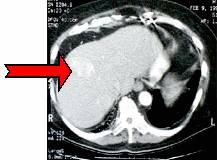

วิธีการนี้จะนิยมใช้ในการทำลายมะเร็งที่ตับ ทั้งแบบปฐมภูมิและแบบทุติยภูมิ โดยวิธีการนี้จะมีข้อดีกว่าการผ่าตัดแบบเดิมที่ใช้การเฉือนก้อนมะเร็งออกไปที่วิธีการนี้จะมีทำลายเนื้อเยื่อดีที่อยู่ในบริเวณใกล้เคียงในปริมาณที่น้อยมาก และถ้าเนื้อเยื่อบริเวณนั้นกลับมาเป็นมะเร็งอีกก็สามารถใช้วิธีการนี้ในการทำลายเนื้อเยื่อมะเร็งใหม่ซ้ำได้อีก นอกจากนี้ยังมีการสูญเสียเลือดที่น้อย มีรอยเปิดของแผลที่มีขนาดเล็กมาก ทำให้ใช้เวลาในการพักฟื้นสั้นไม่ต้องพักที่โรงพยาบาลนาน มีความเสี่ยงในการติดเชื้อที่น้อย มาก มีอัตราการกลับเป็นซ้ำของเนื้องอก (tumor recurrence rate) ที่ต่ำ (ประมาณ 1.8%7) และ อัตราการเกิดภาวะแทรกซ้อน (rate of complication) ที่ต่ำ (ประมาณ 3.6%) และเป็นภาวะแทรกซ้อนที่ไม่รุนแรง8 โดยอาการแทรกซ้อนนั้นได้แก่ การเป็นฝีที่ตับ (abscess) เลือดออก ปอดแฟบ (collapse of lung) หัวใจเต้นผิดจังหวะ และมีรอยไหม้ที่ผิวหนัง ภาพที่ 7 แสดงภาพเนื้อร้ายที่ตับก่อนและหลังจากใช้การรักษาด้วย RFA.

(ก) (ข)

ภาพที่ 7. เนื้อร้ายที่ตับก่อนและหลังจากใช้การรักษาด้วยคลื่นวิทยุ

(ก) เนื้อร้าย (tumor) ก่อนการรักษา

(ข) เนื้อร้ายที่ถูกทำลายด้วยคลื่นวิทยุ จะพบว่ามีขนาดใหญ่กว่าและสีเข้มกว่าเนื้อร้ายที่ยังไม่ถูกทำลาย แต่เมื่อเวลาผ่านไป ขนาดของเนื้อร้ายที่ตายแล้วนี้จะหดลงเพราะร่างกายจะดูดซึมและขับถ่ายเซลล์ที่ตายแล้วออกไป.9